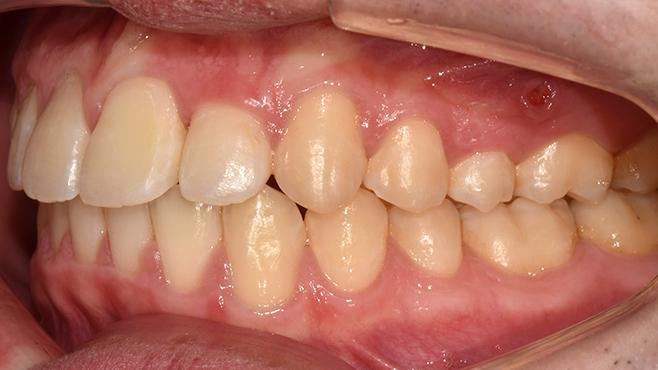

before

after

※ 위 임상사진은 동일조건으로 촬영되었으며, 사진에 대한 별도의 조작이 처리되지 않았습니다.

※ 위 임상사진 및 포트레이트는 환자와의 포괄적인 초상권 계약 이후 사용하고 있습니다.

※ 수술 및 치료과정에서 부작용이 발생할 수 있으므로 충분한 상담과 신중한 판단이 요구됩니다.

실제 치료 사례

수많은 환자들이 고민 끝에 선택한 치료,

그리고 그 후의 놀라운 변화

- ※ 위 임상사진은 365서울원탑치과에서 진료를 시작하고 마친 동일한 환자의 사진입니다.

- ※ 위 임상사진은 동일한 장소에서 동일한 조건으로 촬영되었으며, 사진에 대한 별도의 조작이 처리되지 않았습니다.

- ※ 수술 및 치료 과정에서 부작용이 발생할 수 있으므로 의료진과의 충분한 상담과 신중한 판단이 요구됩니다.